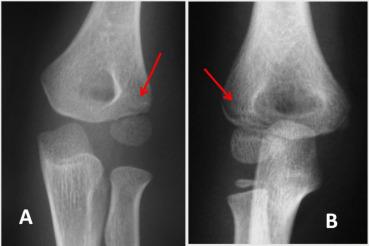

Diagnosis and treatment of displaced humerus lateral condylar fracture is well codified with open reduction and pinning. For non-displaced or minimally displaced lateral condylar (NMDLC) fractures, diagnosis can be challenging because of cartilaginous structures none visualized on radiographs.

We reviewed consecutive NMDLC fractures during 6 years including children younger than 15 years old with displacement lesser than 2 mm (Rigault type I) at initial radiographs divided in two groups: only line fracture was viewed (R1a), displacement gap lesser than 2 mm (R1b). After elbow cast immobilization, children have got MRI. Surgery was performed in complete articular fractures. All children were seen after 1 mouth then at 6 month for elbow evaluation.

Thirty-one fracture, including twenty-two (70.97%) boys. Average age was 6.24 years (3 to 11). Fifteen fractures was classified R1a and sixteen R1b .According to MRI, seven fractures (22,6%) were metaphyseal Gp1, eleven (35,5%) were metaphyso-epiphyseal with an intact hinge cartilage Gp2 ,nine (29%) were complete Salter IV Gp3 and MRI reveals a supracondylar fractures in four cases. Fracture was metaphyseal more often in R1a group (40.0%) compared to R1b (6.3%). Gp3 group was significantly higher in R1b (50.0%) compared to R1a group (6.7%). For the sixteen R1b cases, eight presented articular cartilage involvement on MRI (Gp3) with concordant operative findings.